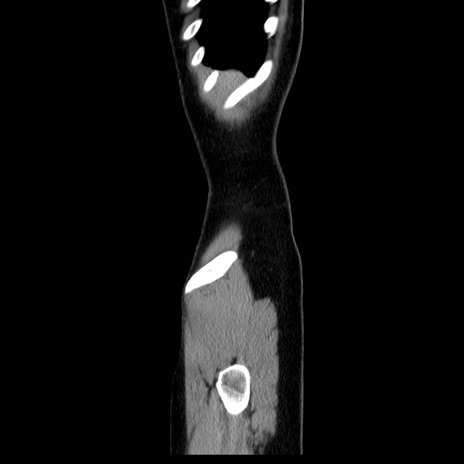

症例39(矢状断像)

【症例】40歳代女性

【主訴】上下腹部痛

【現病歴】2日目から下腹部痛あり。夜間は痛みで眠れなかった。昨日より上腹部痛と下痢が出現。臥位で痛みは軽快したため、休んでいた。本日になって臥位でも立位でも痛みが強くなってきたため救急要請。

【既往歴】子宮内膜症

【身体所見】部:平坦・軟、左上下腹部に圧痛あり、反跳痛あり。

【データ】WBC 21800、CRP 26.78

CT